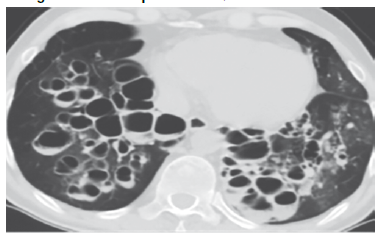

El cuadro N° 4, ilustra la extensión y localización de las BQs, la ubicación de las mismas por segmentos pulmonares muestra que 8 pacientes tienen las lesiones a nivel de un lóbulo pulmonar llámese lóbulo superior e inferior derecho o izquierdo, en 9 casos las lesiones se ubican en dos lóbulos generalmente lóbulos superiores y 6 pacientes calificados como difusos con daño pulmonar importante en toda su estructura, el patrón tomográfico más frecuente fue la variante cilindrica (Figura N°1) en 21 pacientes y la variante sacular o quística (Figura N° 2) en 2 pacientes.

Figura N° 2. Bronquiectasias Quísticas o saculares

FORMACIONES QUÍSTICAS DISEMINADAS AGRUPADAS EN RACIMOS EN AMBOS PULMONES DONDE SE OBSERVA NIVELES HIDROAEREOS

La TTAR permite valorar la extensión, localización y morfología de las BQs, la tabla 4 muestra que estas fueron bilobares en 9 pacientes (39,1%), 8 de ellos tienen los lóbulos superiores afectados y 6 la forma multilobar o difusa, diferentes estudios muestran una mayor prevalencia de la forma cilindrica o tubular33 sobre la forma quística o varicosa, en nuestro estudio destaca nítidamente la forma cilindrica con un 91,3%.